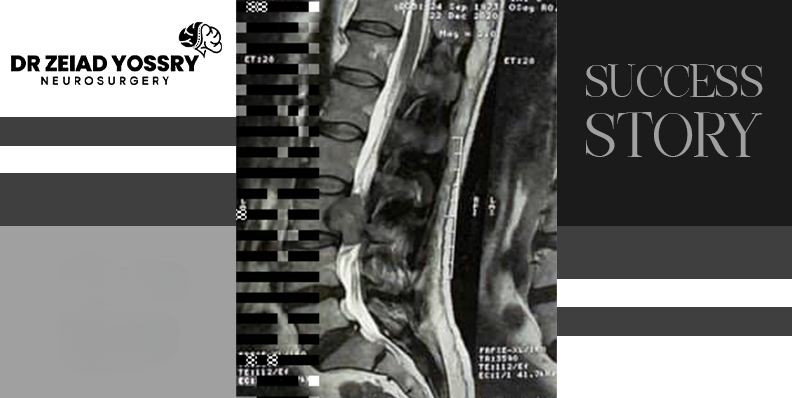

The tests revealed that the patient had a large tumor on the spinal cord, which was compressing the nerves and causing severe symptoms. This tumor had also extended into the back muscles behind the peritoneum (the membrane lining the abdominal cavity), necessitating surgical intervention. Dr. Zeiad Yossry explained to the patient that the spinal cord lies within the spine, protected from injury, and contains bundles of nerves that transmit messages between the brain and nerves throughout the body. A tumor on or near the spinal cord can disrupt this communication, impair function, and seriously threaten health. Therefore, it is important to undergo surgery to permanently remove the tumor.

The goal of spinal tumor treatment is complete removal of the tumor whenever possible. This is often the preferred approach for tumors that can be safely excised. Dr. Zeiad Yossry performed the tumor resection for this patient, a highly precise procedure. With great skill and experience, Dr. Zeiad Yossry was able to completely remove the tumor. The vertebrae were then stabilized using plates and screws, relieving pressure on the surrounding nerves while immediately reconstructing and stabilizing the spine.